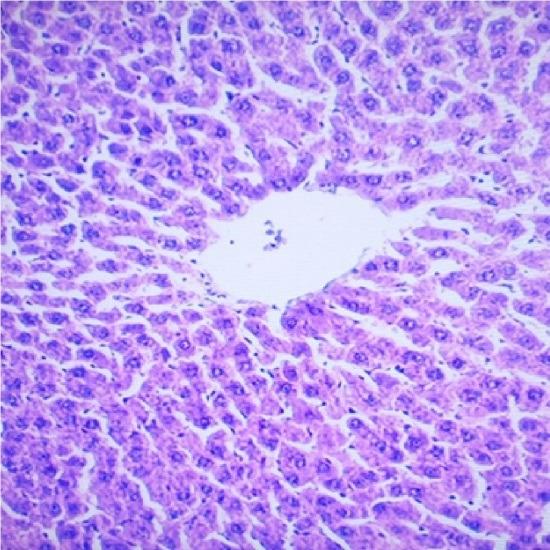

The therapeutic benefit derived from the clinical use of tramadol (TD) has been characterized by hepatotoxicity due to misuse and abuse. The implications of drug-induced hepatotoxicity include socio-economic burden which makes the search for remedy highly imperative. The present study investigated the protective effects of melatonin (MT) and n-acetylcysteine (NAC) on TD-induced hepatotoxicity in albino rats. Forty five adult rats used for this study were divided into nine groups of five rats each. The rats were pretreated with 10mg/kg/day of NAC, 10mg/kg/day of MT and combined doses of NAC and MT prior to the administration of 15 mg/kg/day of TD intraperitoneally for 7 days respectively. At the termination of drug administration, rats were weighed, sacrificed, and serum was extracted and evaluated for liver function parameters. The liver was harvested, weighed and evaluated for oxidative stress indices and liver enzymes. Alanine aminotransferase, alkaline phosphatase, aspartate aminotransferase, total bilirubin, conjugated bilirubin, and malondialdehyde levels were significantly (P<0.05) increased in rats administered with TD when compared to control. Furthermore, glutathione, superoxide dismutase and catalase levels were decreased significantly (P<0.05) in rats administered with TD when compared to control. The Liver of TD-treated rats showed necrosis of hepatocytes. However, the observed biochemical and liver histological alterations in TD-treated rats were attenuated in NAC and MT pretreated rats. Interestingly, pretreatment with combined doses of NAC and MT produced significant (P<0.05) effects on all evaluated parameters in comparison to their individual doses. Based on the findings in this study, melatonin and n- acetylcysteine could be used clinically as remedies for tramadol associated hepatotoxity.

曲马多(TD)临床使用所带来的治疗益处因误用和滥用而表现为肝毒性。药物性肝毒性的影响包括社会经济负担,这使得寻找补救措施迫在眉睫。本研究调查了褪黑素(MT)和N-乙酰半胱氨酸(NAC)对TD诱导的白化大鼠肝毒性的保护作用。本研究使用的45只成年大鼠分为9组,每组5只。在分别腹腔注射15mg/kg/天的TD共7天之前,大鼠分别用10mg/kg/天的NAC、10mg/kg/天的MT以及NAC和MT的联合剂量进行预处理。在药物给药结束时,对大鼠称重、处死,提取血清并评估肝功能参数。摘取肝脏,称重并评估氧化应激指标和肝酶。与对照组相比,给予TD的大鼠丙氨酸氨基转移酶、碱性磷酸酶、天冬氨酸氨基转移酶、总胆红素、结合胆红素和丙二醛水平显著(P<0.05)升高。此外,与对照组相比,给予TD的大鼠谷胱甘肽、超氧化物歧化酶和过氧化氢酶水平显著(P<0.05)降低。TD处理大鼠的肝脏显示肝细胞坏死。然而,在NAC和MT预处理的大鼠中,TD处理大鼠中观察到的生化和肝脏组织学改变有所减轻。有趣的是,与它们的单独剂量相比,NAC和MT联合剂量预处理对所有评估参数均产生显著(P<0.05)影响。基于本研究的结果,褪黑素和N-乙酰半胱氨酸可在临床上用作曲马多相关肝毒性的补救措施。